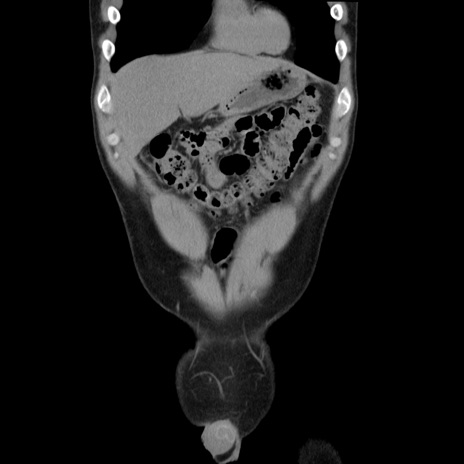

症例36(冠状断像)

【症例】20歳代 男性

【主訴】心窩部痛

【現病歴】今朝より上腹部痛あり。一旦軽快していたが再度出現したため救急要請。昨日夕に白身の魚を含む刺身を食べた。

【身体所見】BP 136/89mmHg、HR 74/min、BT 37.0℃、腹部:膨満、軟、心窩部に圧痛あり。反跳痛なし、筋性防御なし、腸雑音やや亢進あり。

【データ】WBC 17700、CRP 0.48